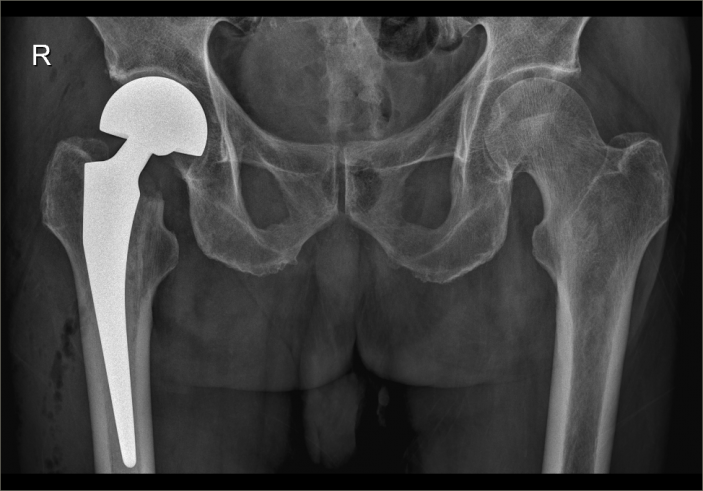

爲了手術能順利開展,骨科主任吳志斌一面邀請我院内科專家會診,對内科疾病進行積極治療,爲手術開展創造有利條件,一面召開術前讨論,精心拟定“右側人工股骨頭置換術”的手術方案,并對術中、術後可能出現的情況制定相應對策。

經過内科對症治療後,患者病情穩定,吳主任帶領團隊抓住時機,在麻醉科的配合下,果斷爲其施術。根據術前拟定方案按部就班實施手術,娴熟地切開組織、修整股骨近端、安裝骨柄假體和雙動股骨頭、複位髋關節,并細心檢查髋部活動度良好、雙下肢等長後,縫合切口順利完成手術。因術前準備充分,整個術程一氣呵成,既縮短手術時間,也減少術中出血,有效降低手術給患者帶來的傷害。